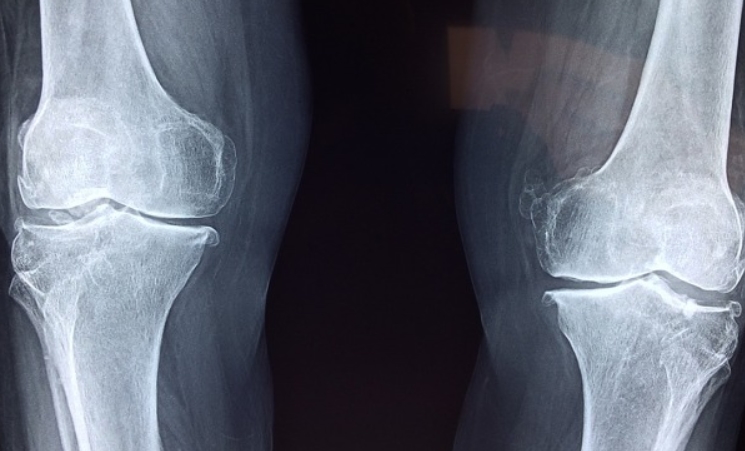

- X-ray, MRI, 초음파 검사: 관절 손상 여부를 확인하기 위해 촬영하는 검사입니다.